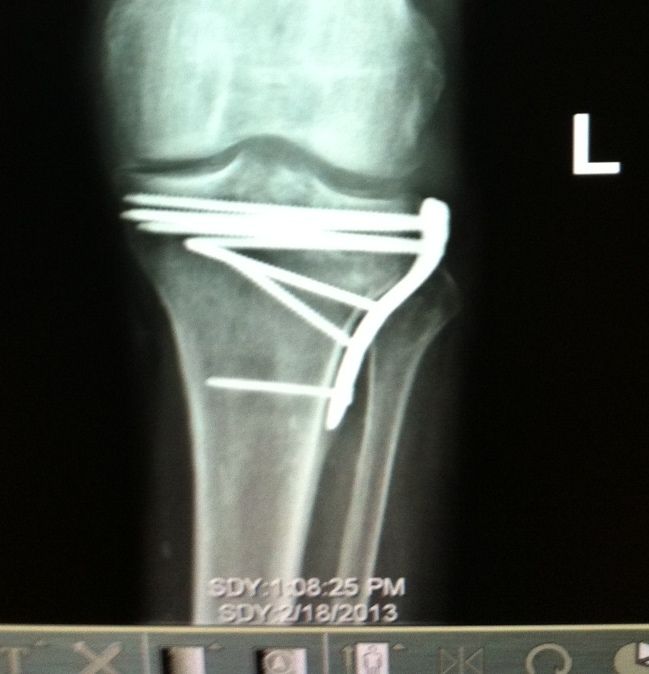

Here's Hubby's Xray from Monday. He says now he has the potential to have a loose screw. I told him that happened before the first accident. :P

The screws are holding together the pieces of the top of that bone. It was in about five pieces, the one on the right side slightly larger, the others - not very big. The bottom screw holds the metal plate in place like a bracket. The plate, as seen from the side, wraps around the top of the bone. You can feel it through his skin, and there's no 'feeling' in that area.